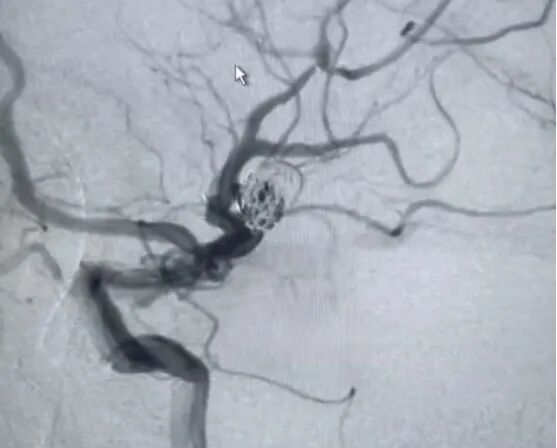

手术如期进行,患者麻醉插管后,脑氧饱和度显示左侧57%,右侧70%,左右相差13%。术中行主动脉弓、双侧颈总动脉、颈内动脉造影。造影所见:Ⅰ型弓,左侧大脑中动脉M1段远端以远未见显影,考虑左侧大脑中动脉M1段栓塞梗死。脑氧饱和度监测结果提示左脑氧饱和度下降,与术中造影结果一致。

(造影提示:大脑中动脉惭1段栓塞梗死,与监护仪结果一致)

行左侧大脑中动脉M1段栓塞取栓术后,发现左侧大脑中动脉远端复通但重度狭窄近闭塞,分叉部见一动脉瘤,瘤nei射血明显,远端血管见显影。考虑狭窄部位随时可能再闭塞,而开通闭塞部位后动脉瘤破裂出血风险较大,故在术中行动脉瘤栓塞并狭窄部位支架置入血管成形。术中栓塞动脉瘤后左边脑氧突然下降至48%,再造影后,发现远端血管未见显影。